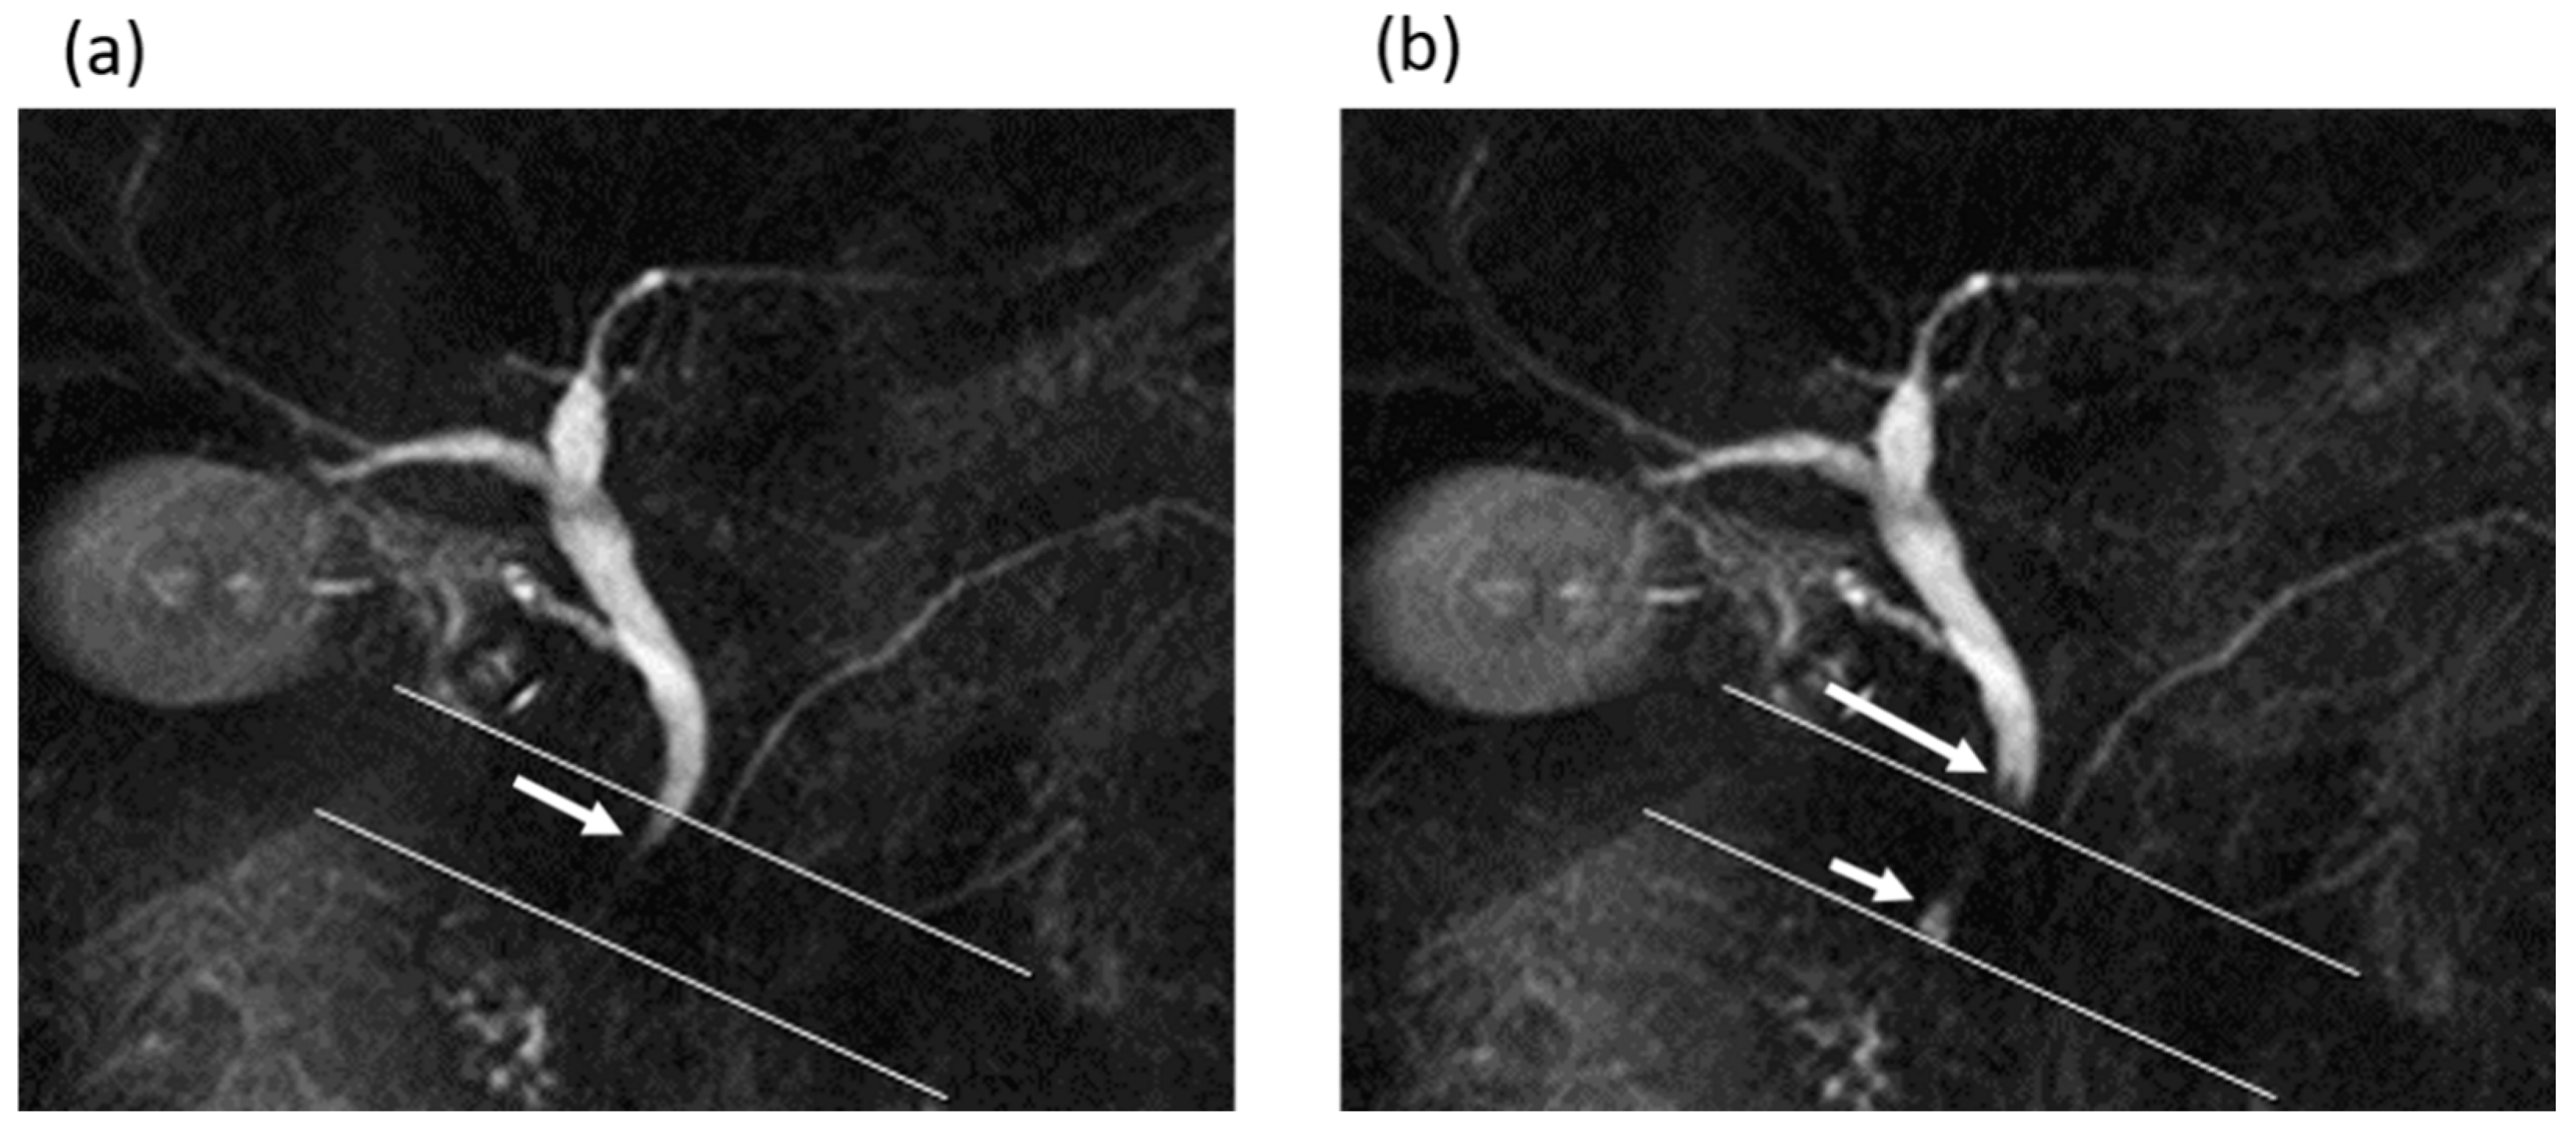

Figure 3.

A 62-year-old man in the gallstone group. (a,b) Cine-dynamic MRCP images with a spatially selective IR pulse. (a) The antegrade bile flow appeared as high signal intensity (arrow) within the area of the IR pulse, showing a grading score of 2. (b) The reverse bile flow was seen as low signal intensity outside the area of the IR pulse (long arrow) and was also seen as high signal intensity coming from duodenal papilla side into the area of the IR pulse (short arrow). The grading score of reverse bile flow was classified as 1.